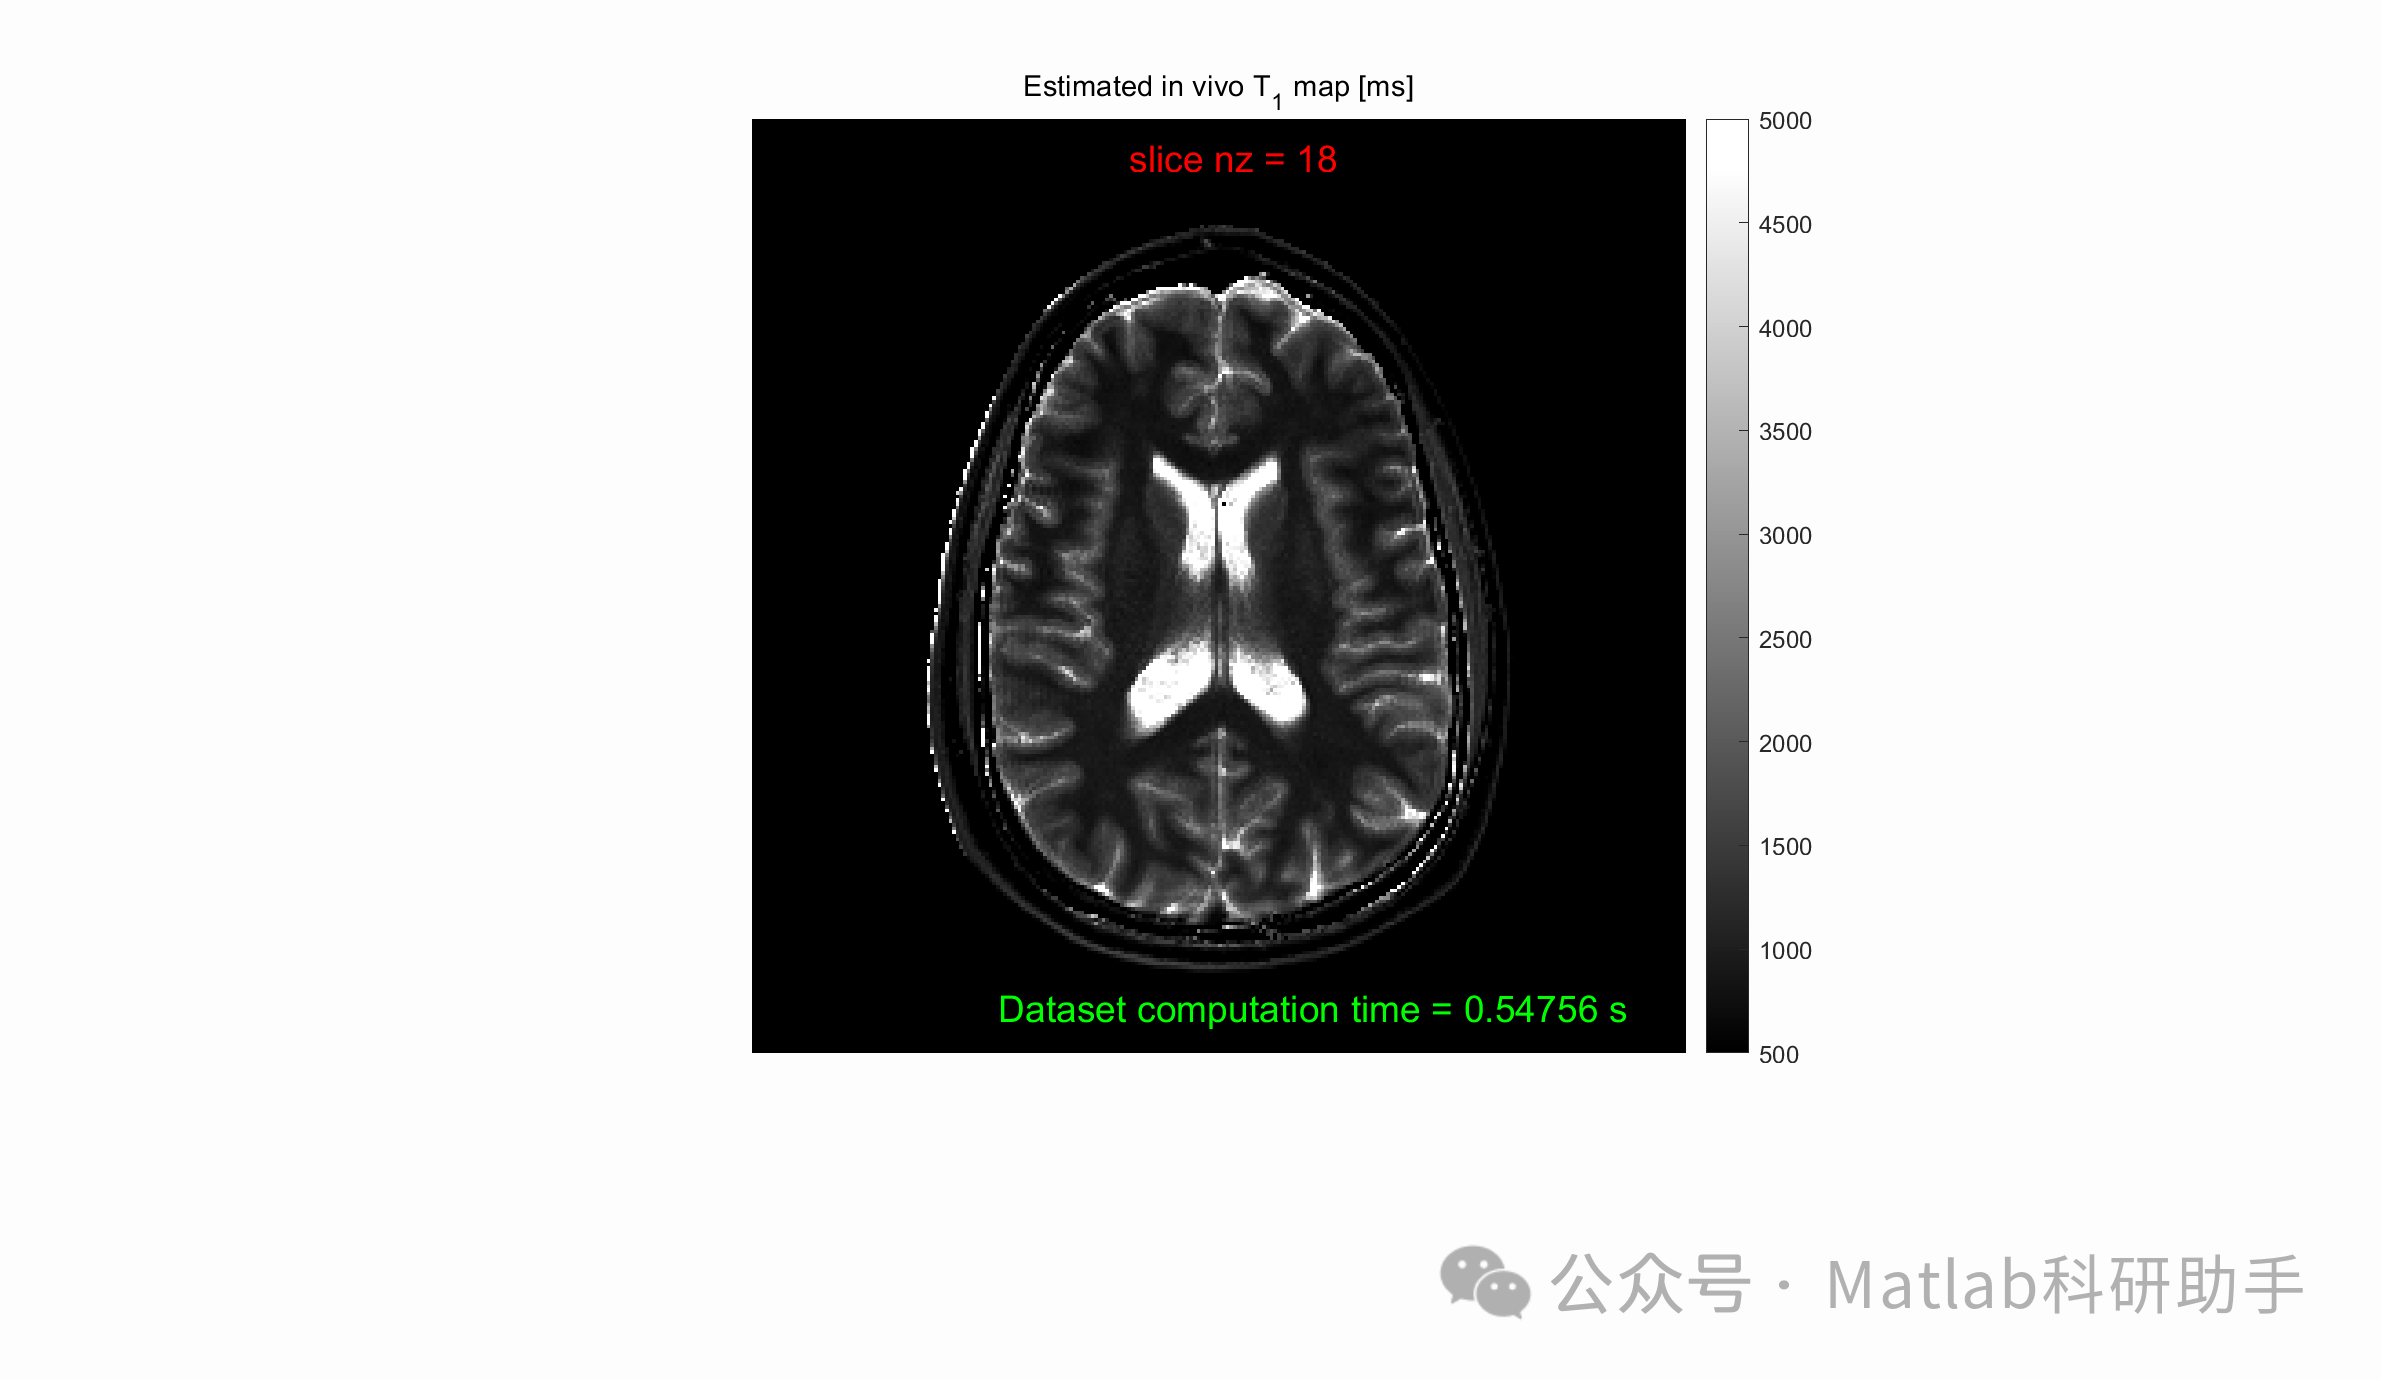

磁共振成像(MRI)作为一种非侵入性的医学成像技术,在临床诊断和科研领域发挥着越来越重要的作用。定量磁共振成像,尤其是变量翻转角(Variable Flip Angle, VFA)技术,可以通过测量信号强度随翻转角变化的规律来估计组织参数,如纵向弛豫时间(T1)。准确且精确的T1值对于鉴别病变组织、评估治疗效果以及指导临床决策至关重要。然而,传统的VFA方法通常耗时较长,限制了其在实际应用中的普及。因此,开发快速、准确且精确的VFA MRI算法成为当前的研究热点。本文将综述近年来在快速VFA MRI算法方面的研究进展,并探讨其面临的挑战与未来发展方向。

VFA MRI 是一种基于梯度回波序列(Gradient Echo, GRE)的定量T1成像技术。其基本原理是,通过在不同的翻转角下采集GRE信号,利用Bloch方程或其他简化模型来拟合信号强度与翻转角之间的关系,从而求解出T1值。具体来说,GRE信号的强度与T1、T2*、重复时间(TR)以及翻转角(α)等参数相关。在较短的TR条件下,T2*的影响可以忽略不计,并且信号强度可以近似简化为关于T1和α的函数。通过选择多个不同的翻转角,获得一系列的信号强度数据,即可利用非线性拟合或线性化方法求解T1值。

⛳️ 运行结果